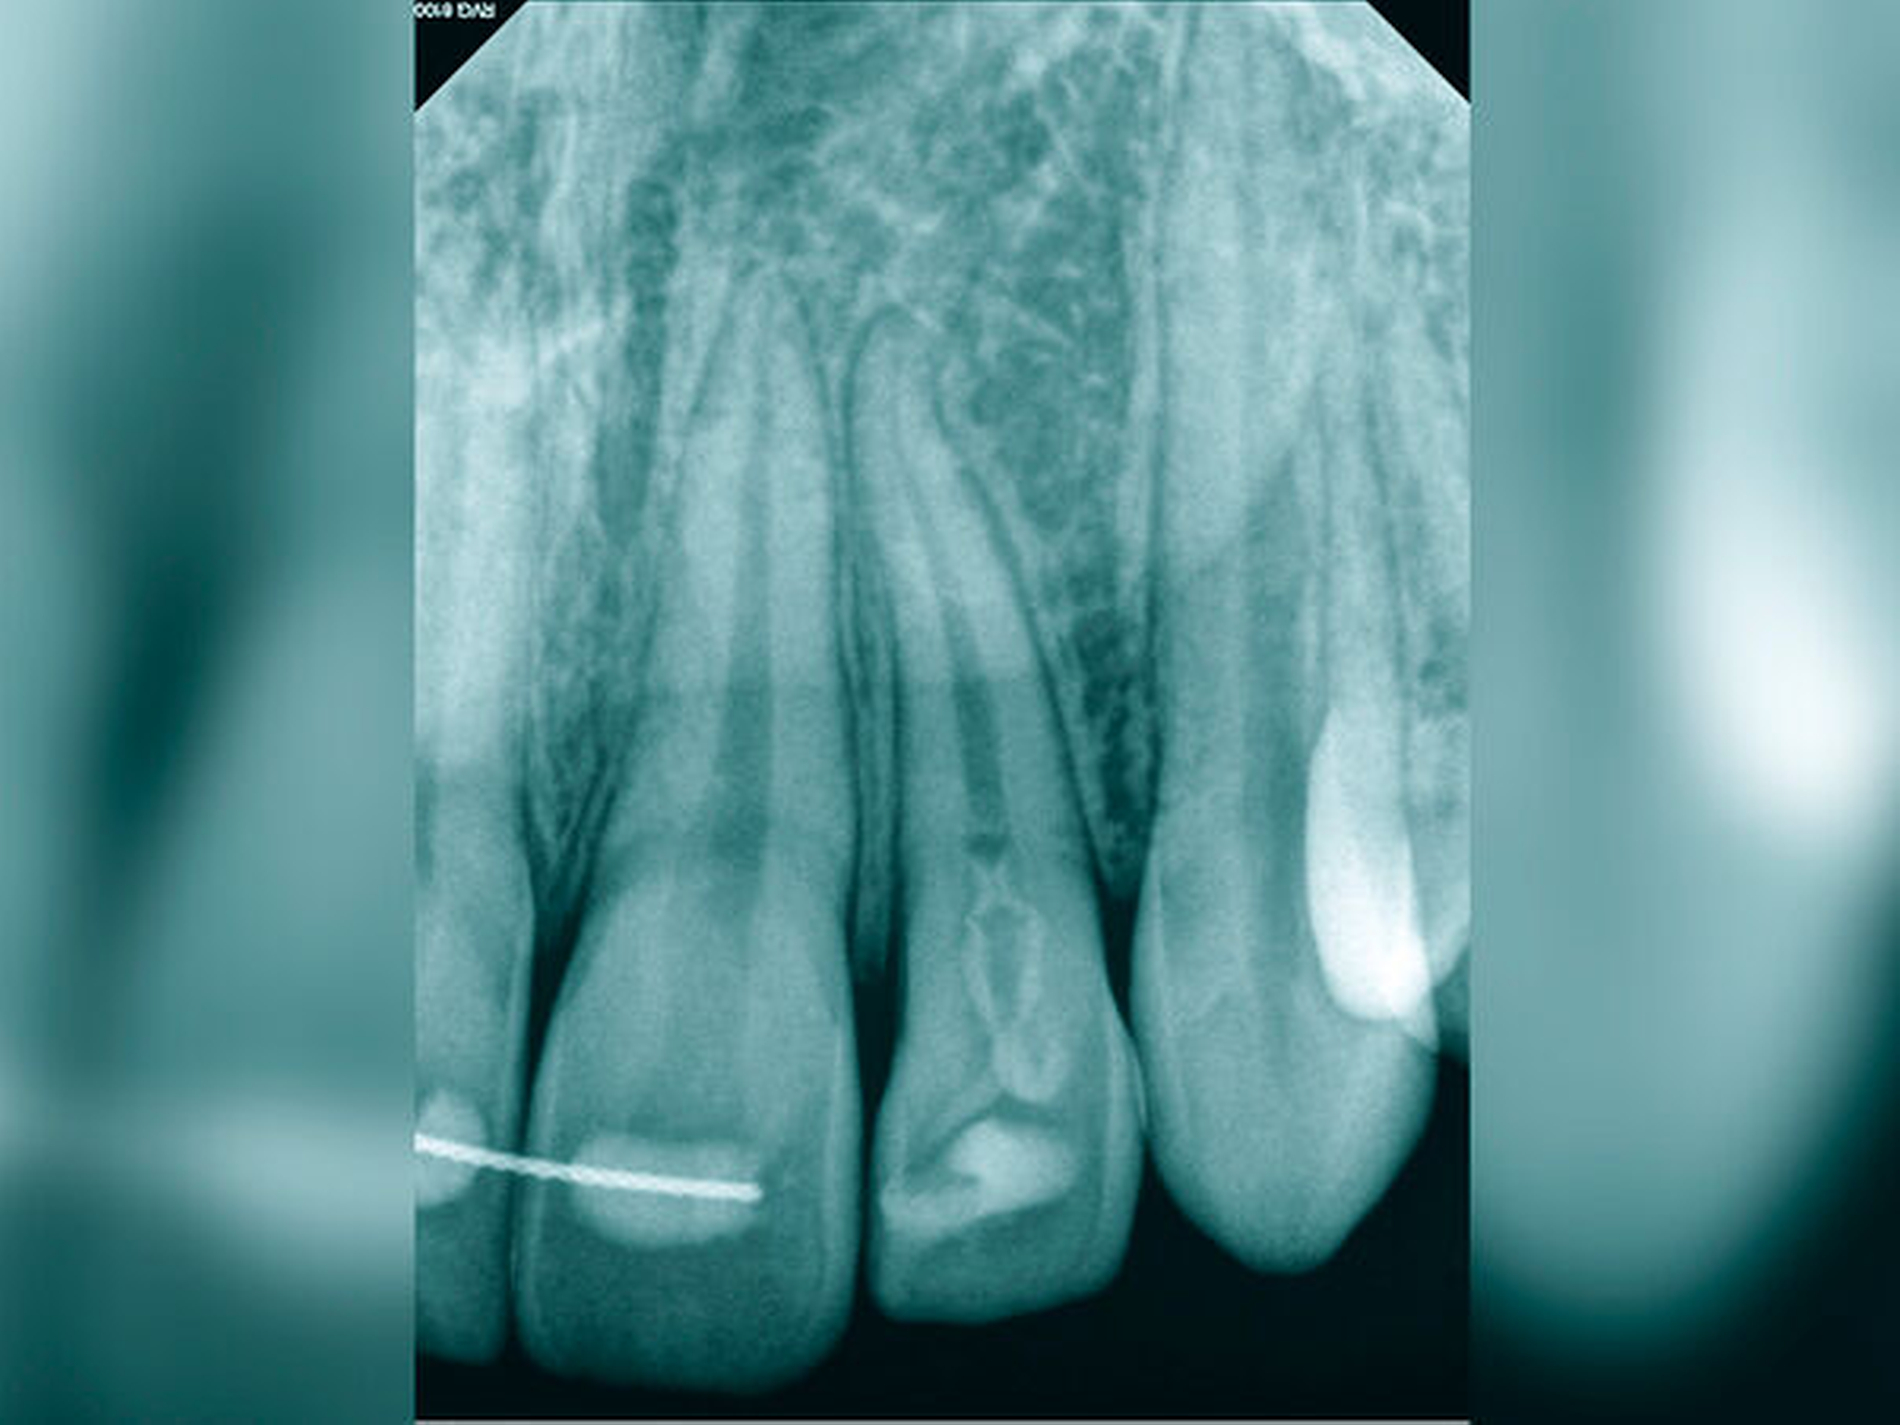

Nach klinischer und radiologischer Untersuchung wurde am Zahn 45 eine irreversible Pulpitis diagnostiziert. Anamnestisch konnten Komplikationen ausgeschlossen werden. Die klinischen Befunde waren eindeutig auf den Zahn 45 lokalisierbar. Der auf der Röntgenaufnahme geradlinige und vollständig bis zum Apex verfolgbare Wurzelkanal ließ einen normalen Schwierigkeitsgrad bei sehr guter Prognose erwarten (Abbildung 11a).

Die Therapie erfolgte unter Verwendung von Kofferdam und Lupenbrille. Die mechanische Erweiterung des Wurzelkanals und die Wurzelkanalfüllung erfolgten nach elektrometrischer und röntgenologischer Arbeitslängenbestimmung (Abbildungen 11b und 11c). Nach Abschluss der Wurzelkanalbehandlung war die Patientin beschwerdefrei.